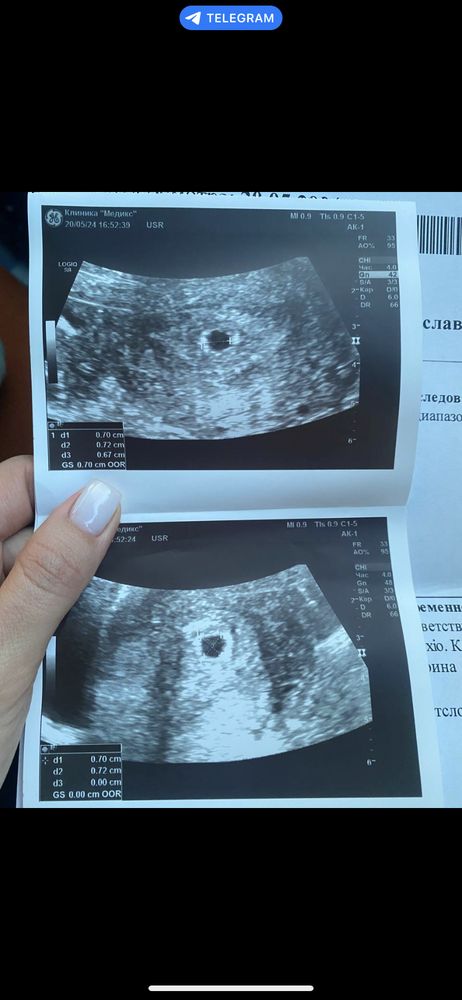

Узи 5 недель ровно , врачу не нравится пя

врачу не нравится мои размеры пя и желточного мешочка,на сроке 5 недель

врач говорит увеличение жм может говорить о анамалии развития плода , эмбрион не увидели